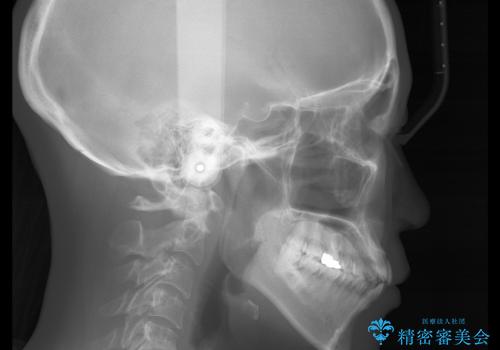

- 歯ぐきと骨が薄く、他院にて大きな矯正治療を断られた患者様です。

ワイヤー治療で行う場合、抜歯治療が第一選択となりますが、

骨と歯茎の状態を考慮した場合、抜歯をして大きく動かすことは避けたいと考えました。

そこで、インビザライン矯正で非抜歯で行うことを提案させて頂きました。

抜歯を行うことが困難であり、また歯ぐきと骨が薄いことで

拡大と呼ばれる歯のアーチを広げる処置を行うことも困難でした。